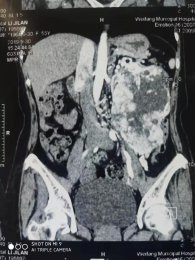

•   鏡益求精|我院泌尿外科腹腔鏡微創(chuàng)為患者切除左腎巨大腫瘤 日期:2019-10-18 16:41:25 點(diǎn)擊:1941 好評(píng):35

隨著生活水平的提高,人民群眾對(duì)健康生活的要求不斷提高,許多人養(yǎng)成了定期查體的好習(xí)慣,通過查體往往能發(fā)現(xiàn)許多疾病的苗頭并加以預(yù)防。但也有部分健康意識(shí)較淡薄或工作繁忙的的朋友,沒有主動(dòng)自覺查體的...